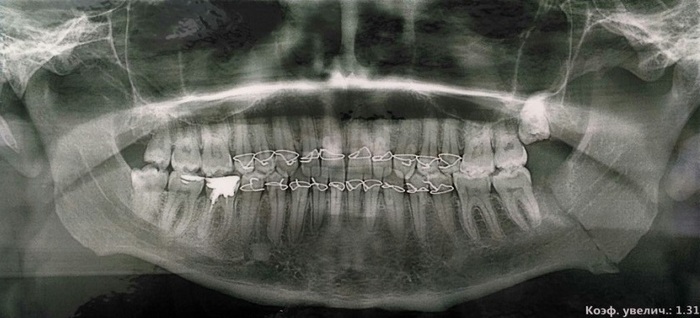

Перелом нижней челюсти. Мифы и реальность (фото)

Когда получил перелом челюсти - очень расстроился. Боль, шинирование, удаление зуба мудрости, есть только жидкую пищу и то через трубочку. Даже носом курить пытался, чтобы не кровил шов. Страх один. (мелкая фотография не моя, но зуб в линии перелома находился примерно так)

Начитался в интернете всякого, посмотрел на "напарников" по палате - совсем духом поник. Спасался чтением интересных статеек, играми в мобильном и просмотром фильмов на тв (принес в палату телек). Решил поделиться опытом с читателями, ибо травма эта очень неприятная. А лечиться нужно.

1. Самое главное - отвлечься от ситуации и не пытаться шевелить челюстью!!! Курить лучше (если вы страдаете от этой пагубной привычки) спустя день-два после операции (можно и в день операции курить, но не много!!! это мешает заживлению шва и может кровь пойти!!!). После курения нужно полоскать зубы, чтобы налёта было меньше. Хлоргикседин (который рекомендуют врачи) хорошо помогает убивать микробы во рту, но вот против налета он бессилен. Рекомендую купить полоскалку для рта типа "Фтородент". Она стоит примерно 80 руб.

2. Кушать надо!!! Даже если не хочется. Лучше употреблять что-то калорийное - детское питание (в нем очень много витаминов. правда его нужно солить и специи мелкие добавлять) подходит для этого отлично. Подойдут так же: бульоны (особенно наваристые, в них много веществ сопутствующих восстановлению) соки с мякотью, кефир, сгущённое молоко. Если нет отверстий между зубами - блендер вам в помощь. Я даже йогурты через него пропускал, чтобы куски фруктов не застревали во рту. После еды обязательно полощите рот и чистите зубы (хотя бы там, где это возможно). Так вы поможете и полости рта и эмали, которая очень страдает. Еще желе и кисели нужно пить, в них много желатина!!! Алкоголь пить не рекомендую, ибо организм ослаблен!

3. Приём лекарств. Первые 10 дней вам будут колоть антибиотики. Зад, после этой процедуры, лучше греть грелкой, ибо антибиотики довольно жесткие и могут появиться шишки. Обезбаливающим лучше не злоупотреблять, потому что оно не является чем-то полезным для организма. После курса уколов, врачи назначают электрофарез с калий-йодом, но многие на него не ходят. А зря!!! Благодаря фарезу уменьшается отек тканей, да и ощущения после него лучше. После этого вам назначат ещё какой-нибудь костный антибиотик (горький до невозможности, но пить его нужно!!! соком можно запить!!!) Он накапливается в кости и спасает ее от остеомиелита. И кальций!!! Его можно разбавлять в воде и пить, пить, пить. Еще врачи делают компрессы с диксидином, он так же снимает воспаление. Лучше еще и шарфом голову замотать, чтобы в тепле была (дело зимой было).

4. Сон. Первую неделю лучше спать на спине. Две подушки (небольшие) очень помогают удобно уложить голову (на боку челюсть болела и отекала). А потом и на боку нормально, только зубы могут по утрам болеть из за железа.

5. Сроки. Лечение длиться от 4 до 6 недель, это если перелом простой. Я ходил с железом ровно 30 дней.

6. Вес. Был 99 кг, стал 87 кг. Слабости нет, чувства голода особо не испытывал.

7. Если челюсть двигается или скрипит. У меня перелом зафиксировался только на 16 день после травмы. До этого челюсть побаливала и клацала. Очень неприятное ощущение. Чтобы такого не было - старайтесь не напрягать рот. Станет она на свое место.

8. Отёк. Отек проходит на 10 - 14 день. У меня был 16 дней. После этого еще может в ухо болью постреливать. Всё это не сильно страшно.

9. Зубы. Зубы могут потемнеть, особенно если вы курите. Зубы могут шататься. Не переживайте, всё норм. У всех так. Возможно, что после лечения брекеты поставить придется (если искривятся от железа), но это не так уж страшно.

10. Туалет. Если мало едите, то и ходить нечем. Не страшно.

11. Больница. В больнице нужно лежать 14 - 21 день. Как врач решит.

12. Снятие шины. Доставать их больно, но терпимо. После этого прикус может быть нарушен. Нужно подождать недели две, должен сам исправиться. Зубы могут болеть и шататься тоже недели две.

13. Снятие налета. Лучше проконсультироваться со стоматологом. Я решил снимать через неделю после снятия шин. Не приятно, но терпимо.

14. Еда. Лучше есть мягкую еду. Челюсть не напрягать. Кость заживает примерно пол года.

Будьте здоровы, друзья!